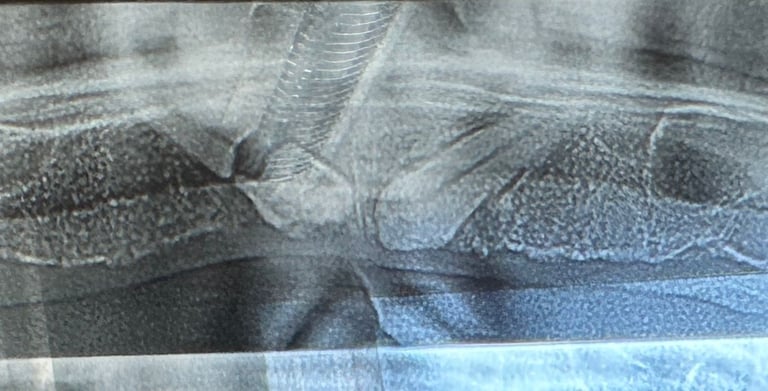

Reabilitare implantara in cazul unor dinti restanti irecuperabili, cu mobilitate severa. Dupa extractia atraumatica a dintilor compromisi, tratamentul continua cu inserarea implanturilor dentare. In prealabil, in urma cu 6 luni s-a realizat aditie osoasa prin sinus lift extern la nivelul cadranului II, tehnica chirurgicala care ne-a permis inserarea implanturile posterioare.